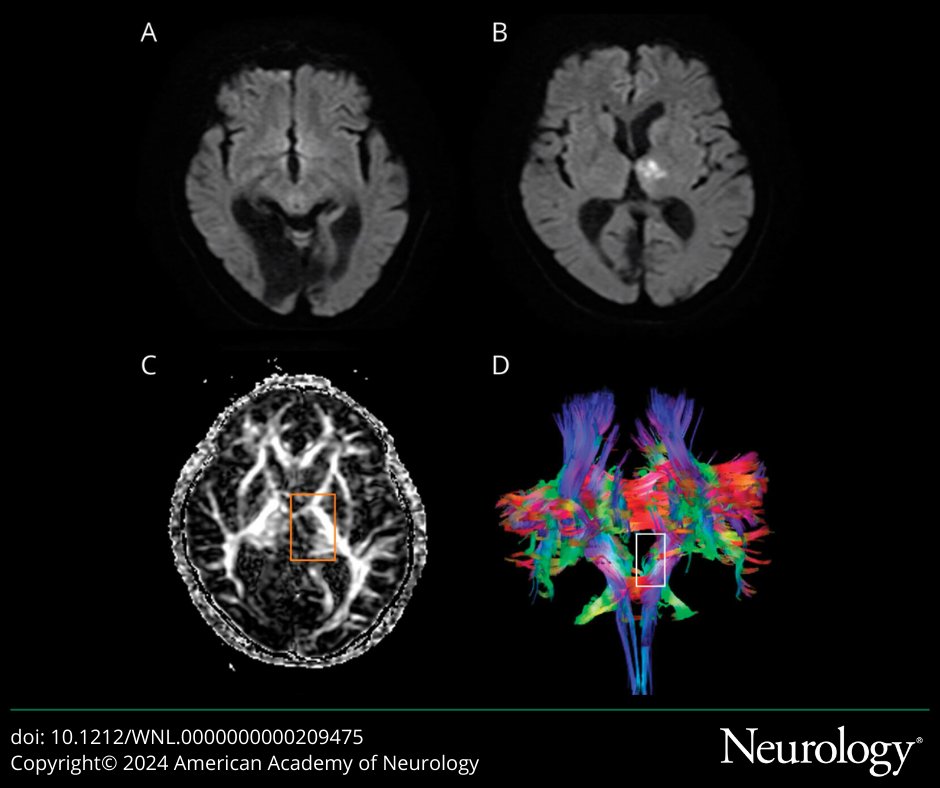

Neurology Journal (@greenjournal) 's Twitter Profile Photo

A 64-year-old woman presented with 18 months of progressive scalp-neck dysesthesias, left leg weakness, and urinary urgency. Read more: hubs.la/Q03hKGRg0 #NeuroTwitter #NeuroX

A 64-year-old woman presented with 18 months of progressive scalp-neck dysesthesias, left leg weakness, and urinary urgency. Read more: hubs.la/Q03hKGRg0

#NeuroTwitter #NeuroX